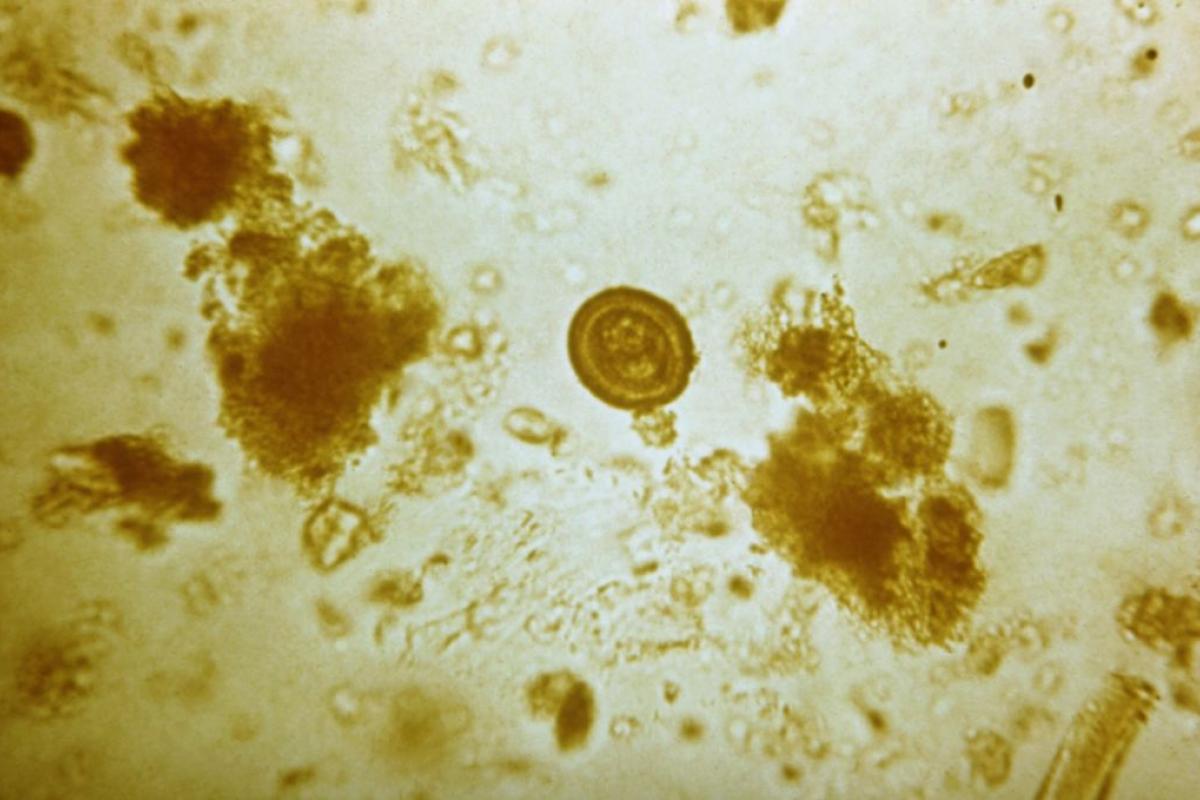

Una radiografía que da miedo. El doctor norteamericano Sam Ghali compartió el pasado 16 de enero en sus redes sociales la impresionante imagen de la pelvis de un hombre que tenía cientos de huevos de un parásito plano que habita en el intestino humano. "Es una de las radiografías más locas que he visto en mi vida", ha señalado el médico.

Las impactantes imágenes mostraban una enfermedad parasitaria llamada cisticercosis. Dicha dolencia es causada por la ingestión de huevos de la T solium. Estos se encuentran en los alimentos contaminados. La autoinfección se presenta cuando una persona ya infectada con T solium adulto ingiere luego los huevos. Esto ocurre por no lavarse bien las manos después de una deposición (transmisión fecal-oral).